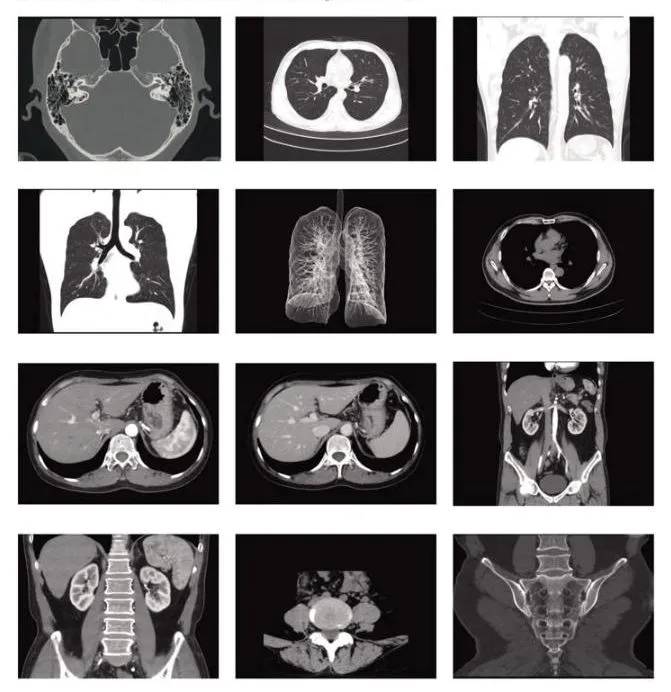

Radiologic 16 Slice Spiral CT Scanner with Cardiac CT Scan Capability. This system offers sub-second full 360-degree scanning, a 2X10mm dual slice high-efficiency detector, and automatic film handling and sending. An affordable and reliable system with future-oriented technology.

It is a sub-second, sub-millimeter acquisition system adapted for economical day-to-day clinical routine. The system offers the latest developments in CT technology for superb image quality and dose efficiency.